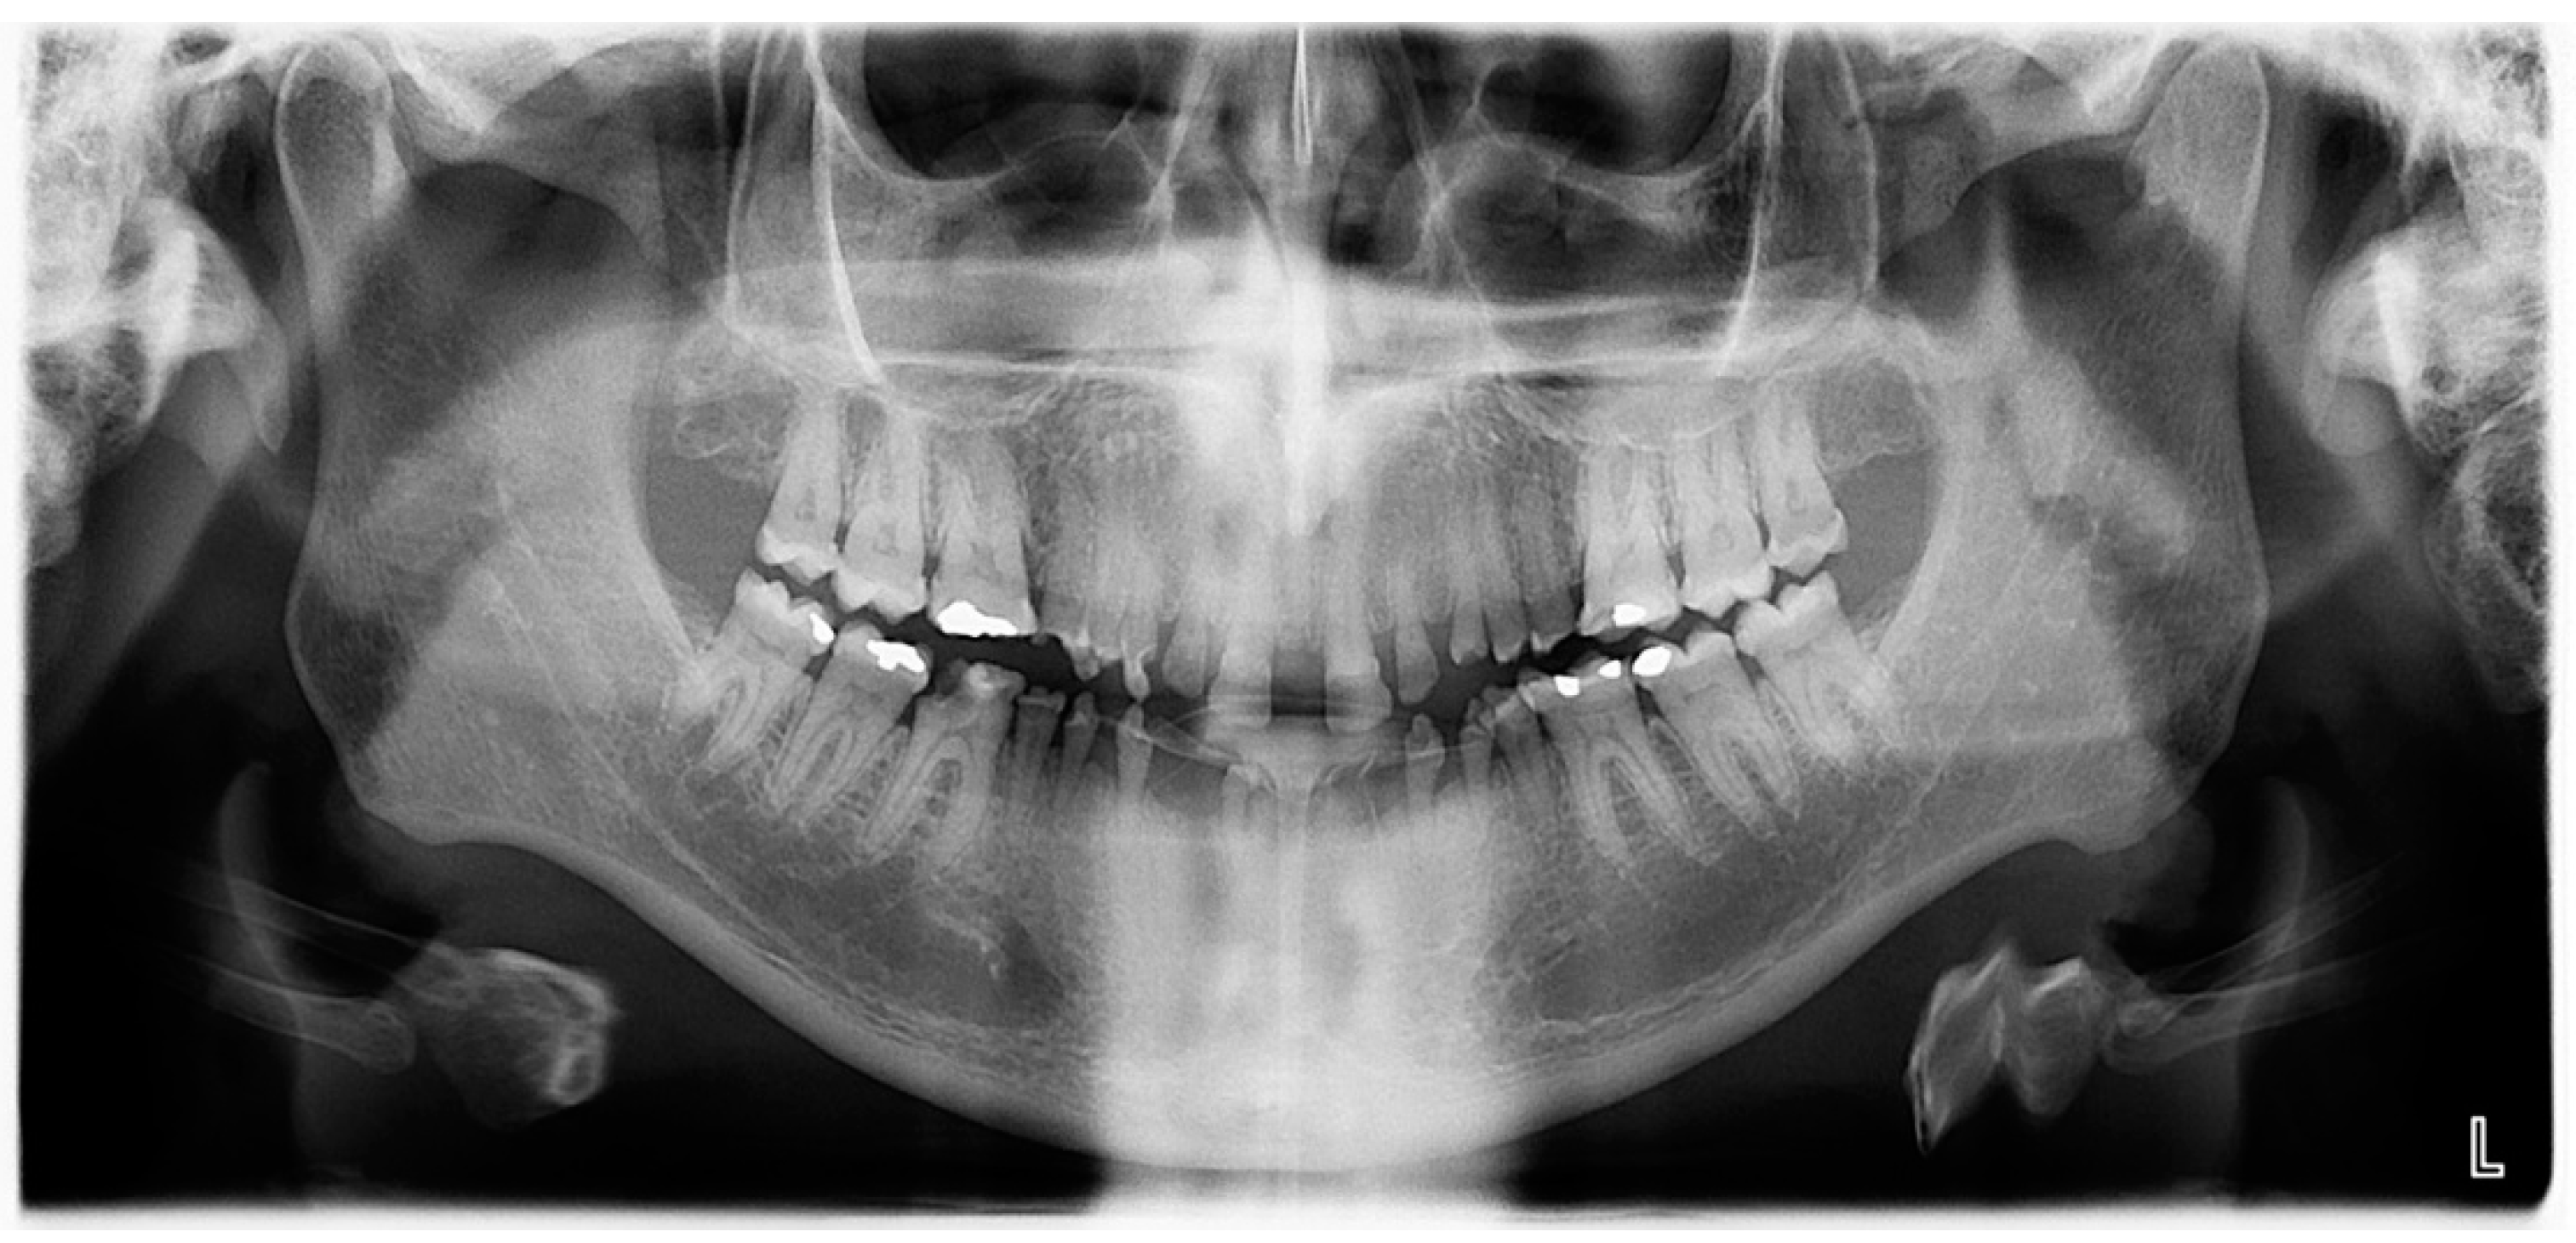

2.1. Clinical and Radiological Examination

- Pre-prosthetic care: exodontia, endodontic and restorative treatments were performed under general anesthesia. The following procedures were performed: endodontic treatment and bonded amalgam restorations for overdenture abutments of teeth numbers 11, 14, 15, 21, 24, 25 and 45 and exodontia of 46, 44, 43, 41, 33, 34, 35, 23, 22, 13 and 12 (Figure 6). The TRPD were placed on the day of surgery and a postoperative consultation was performed the following day to evaluate and adjust the prostheses (Figure 7).